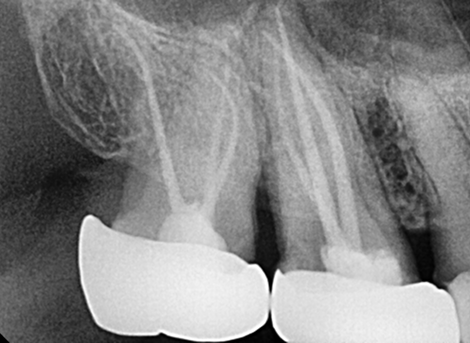

HOW ROOT CANAL WORKS

Your tooth is saved in 4 simple steps

Diagnosis & X-Ray

Diagnosis & Preparation

Laser Cleaning